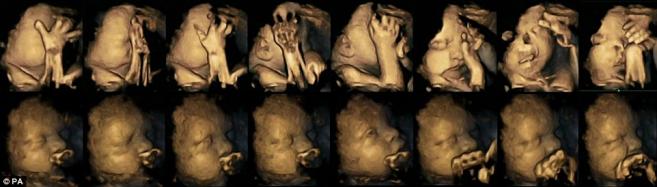

На фотографијата во двата реда се наоѓаат 2 различни бебиња во 32-ра недела од бременоста. Мајката на бебето во горниот ред е пушач, а бебето во долниот ред има мајка непушач. Бебето чија мајка пуши многу почесто си го допира лицето и устата и прави фацијални движења, што индицира на забавен развој.

Таа надгледувала 20 мајки, од кои 4 пушеле просечно по 14 цигари дневно. По проучувањето на ултравукот во 24,28,32и 36 недела се покажало дека бебињата на мајките, кои пушеле покажале значително повисока стапка на допирање на устата и движења на лицето од оние бебиња, чии мајки не пушеле.